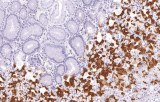

IHC using CE/IVD primary antibodies is a cornerstone in the characterization of gastrointestinal tumors. These antibodies assist pathologists in distinguishing epithelial from mesenchymal origins, determining tumor subtypes, and identifying primary sites in metastatic disease.

- In gastrointestinal stromal tumors (GISTs), KIT (CD117) expression is reliably detected by IHC, while PDGFRA mutations are evaluated through molecular testing, aiding in targeted therapy decisions.